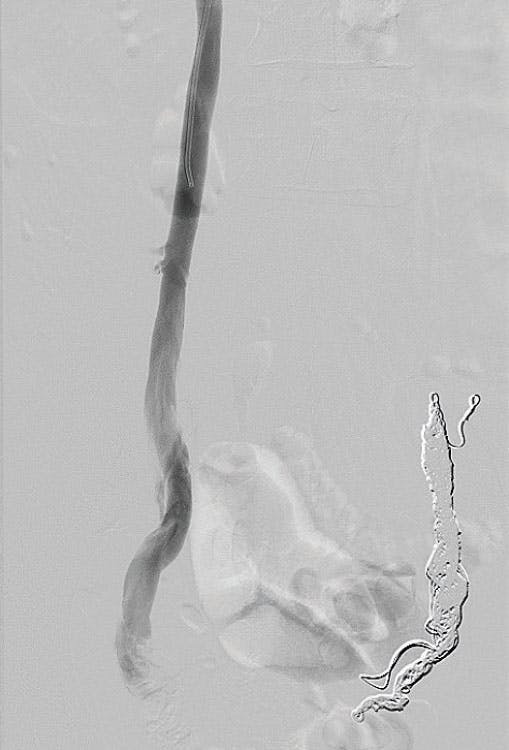

The patient underwent left ovarian vein embolization using Ruby® Coils (Penumbra, Inc.), with complete resolution of her left-sided pelvic pain. However, at follow-up, she reported persistent, moderate right-sided pain. Given dilation of the right ovarian vein on her original imaging (Figure 1), she was brought back for diagnostic venography and subsequent right ovarian vein embolization. It is important to note that the dilated right ovarian vein is less likely to show reflux on CT imaging, even when venous timed. In this case, the right ovarian vein did light up on CT (Figure 2) but much less so when compared with the left ovarian vein.

Figure 1. Preoperative image from before the second procedure showing large dilated right ovarian vein (arrow).

Figure 2. Initial venogram of very large, dilated right ovarian vein.

For this second procedure, Ruby XL Coils were selected. Although a similar packed volume was required, only three coils were needed compared with 10 coils on the left. This reduced both procedure time and cost without compromising effectiveness.

At follow-up, the patient reported complete resolution of all pelvic symptoms and expressed high satisfaction with her outcome (Figure 3).

Figure 3. Postembolization venogram showing bilateral ovarian vein coil embolization with no distal reflux into the pelvic varicosities.